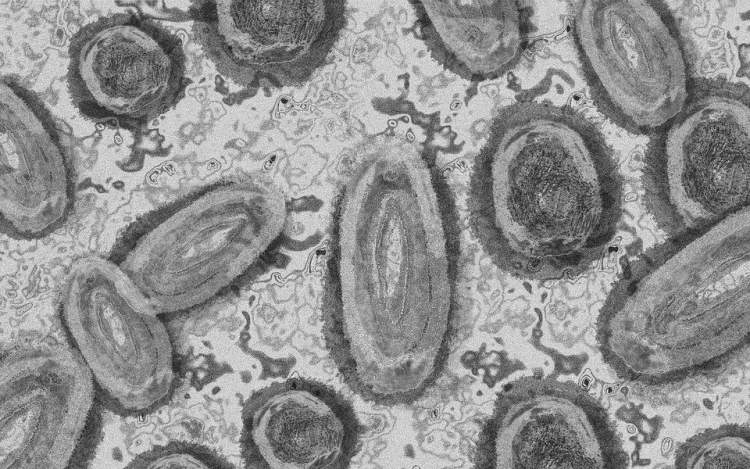

Forrás: mti/illusztráció: pixabay

Egy 3 év alatti gyermek fertőződött meg majomhimlővel Belgiumban

Belgiumban egy 3 év alatti gyermek fertőződött meg majomhimlővel - számolt be róla szerdán a Sudinfo hírportál.